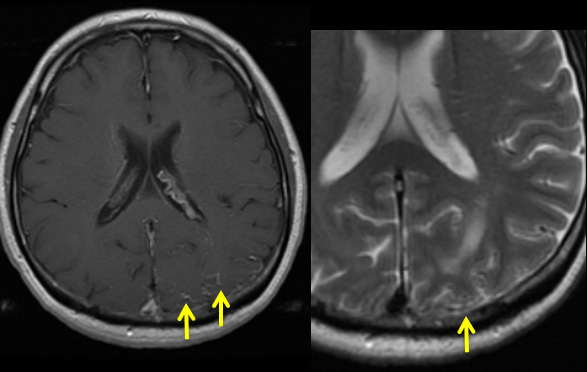

• 病変尾側に拡張した血管(+)

• 硬膜動静脈瘻による静脈性梗塞疑い

• 皮質静脈の逆流はflow void、静脈の増強効果として描出される